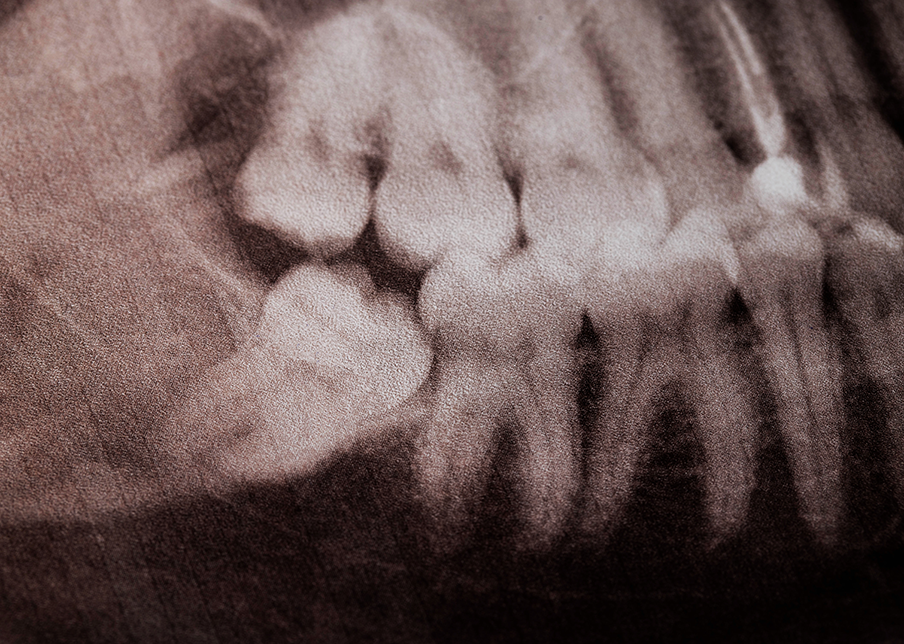

Next, the dentist will carefully extract the impacted wisdom teeth. If the teeth are fully erupted, the procedure may be straightforward. However, if they are impacted beneath the gum line or in the jawbone, incisions may be necessary, and some bone might need to be removed to access the teeth.

“Impacted” wisdom teeth are those that haven’t fully erupted or grown into the proper position. Lack of space can cause them to become trapped, leading to pain, swelling, and potential infections. They can also affect neighbouring teeth. Dentists often suggest removing impacted wisdom teeth through surgery to prevent complications.

The most definitive way to determine if your wisdom teeth are impacted is through dental X-rays. A dentist can evaluate the position of the teeth and recommend treatment based on their findings. If you experience any of these symptoms or suspect that your wisdom teeth may be impacted, consulting with a dentist for a professional evaluation is essential.